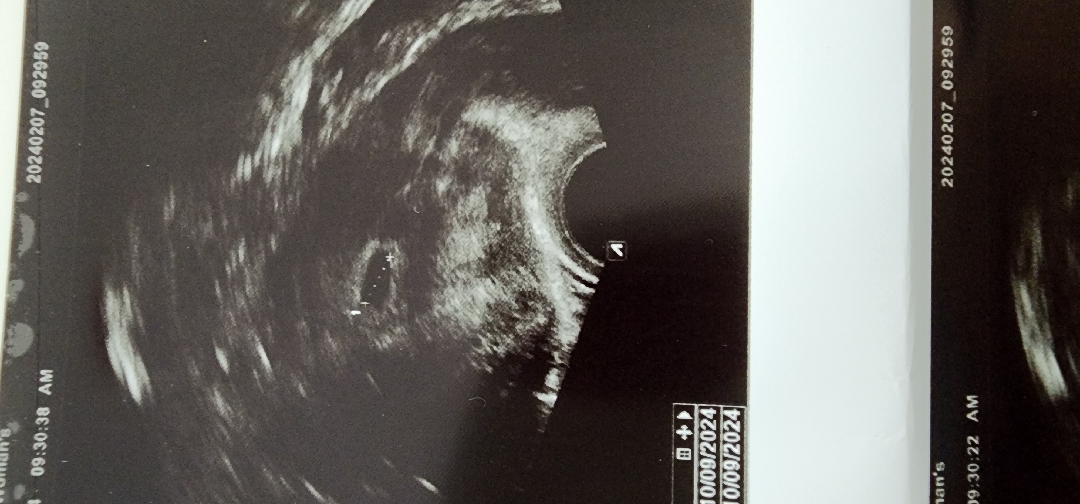

초음파 보고왔어요

네이버 주 수로는 6주4일이라 심장소리 들을수 있을줄 알았는데 ㅎㅅㅎ 너무 기대했나봐용 초음파보구 선생님이 5주에서 6주 인것같다고 애기집은 보인데요 작년 계류유산때 소파술도 깔끔하게 잘되었다고.. 산모가 나이가 있어서 걱정은 하셨대요 그래도 자연 임신도 되고 위치가 좋다고 하시니 그걸로 위안삼아 피뽑고 산전검사 하고 영양제 상담하고 왔어요 다음 진료때는 건강한 젤리곰도 볼수 있으면 좋겠네요